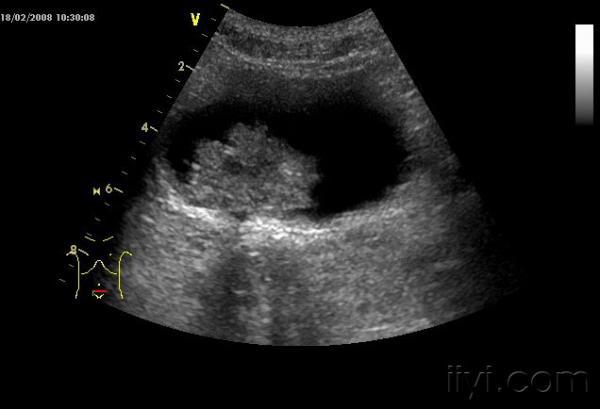

典型膀胱癌声像图一例

男,53岁,10余天前出现肉眼血尿,不混血块,伴下腹痛痛,无发热

[ 本帖最后由 cdk1234555 于 2008-4-5 16:13 编辑 ] 膀胱肿瘤